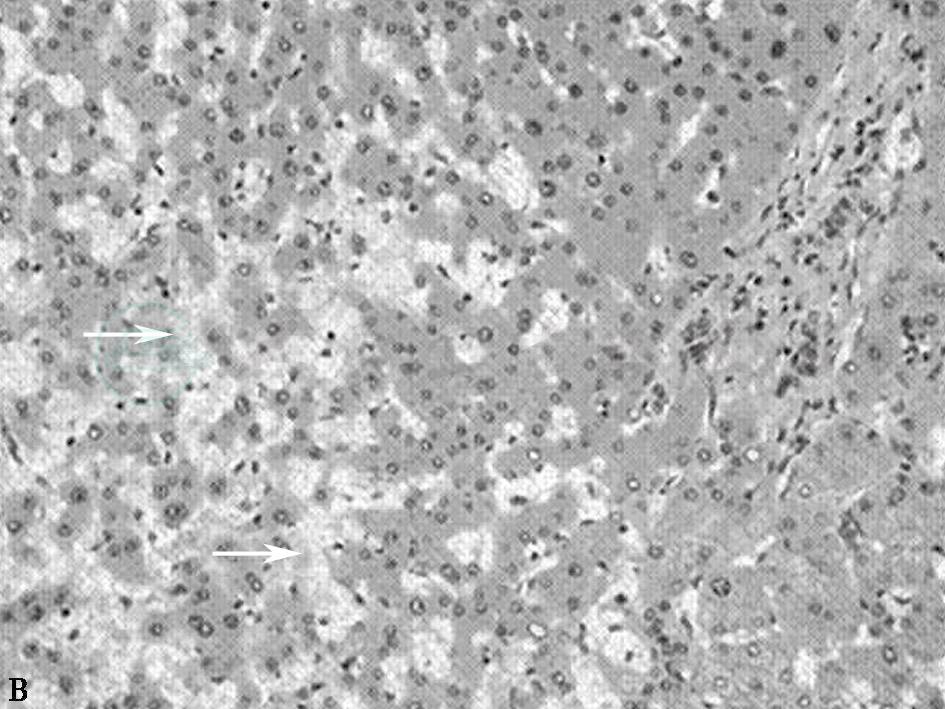

不同病因导致的HSOS病理表现相似,肝窦淤血扩张,病变多见于小叶中心区域(Ⅲ区),并可连接成为充血带。肝窦周围可见大量红细胞以及渗出物沉积并可导致肝窦壁破裂。小叶中央静脉内皮细胞变圆,可出现内膜出血。可以出现小叶中央静脉闭塞和纤维化,其程度与病情相关,肝细胞变性不明显(见图1)。

图1B 肝窦阻塞综合征病理图

肝窦阻塞综合征病理图(×400)。白色箭头所示为肝血窦扩张、淤血;黑色箭头所示为汇管区